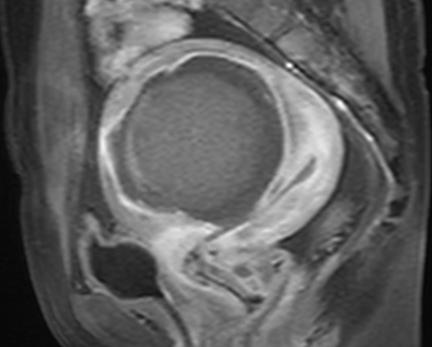

黑色部分就是被灭活的肌瘤,在增强MRI上显示为无灌注。